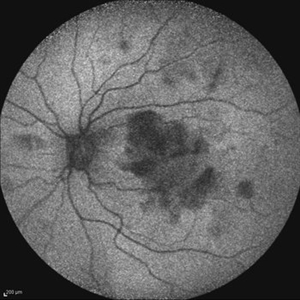

Behcet's Disease Behcet's DiseaseMar 13 2013 by Hamid Ahmadieh, MD Early phase FA of the right eye of a 23-year-old man with retinal vasculitis and branch retinal vein occlusion (BRVO) due to Behcet's disease . Photographer: Solmaz Shahmohammad, Negah Eye Center, Tehran Imaging device: Heidelberg Spectralis Condition/keywords: branch retinal vein occlusion (BRVO), retinal vasculitis

Behcet's Disease Behcet's DiseaseMar 13 2013 by Hamid Ahmadieh, MD Mid phase FA of the right eye of a 23-year-old man with retinal vasculitis and branch retinal vein occlusion (BRVO) due to Behcet's disease . Photographer: Solmaz Shahmohammad, Negah Eye Center, Tehran Imaging device: Heidelberg Spectralis Condition/keywords: branch retinal vein occlusion (BRVO), retinal vasculitis

Behcet's Disease Behcet's DiseaseMar 13 2013 by Hamid Ahmadieh, MD Late phase FA of the right eye of a 23-year-old man with retinal vasculitis and branch retinal vein occlusion (BRVO) due to Behcet's disease . Photographer: Solmaz Shahmohammad, Negah Eye Center, Tehran Imaging device: Heidelberg Spectralis Condition/keywords: branch retinal vein occlusion (BRVO), retinal vasculitis